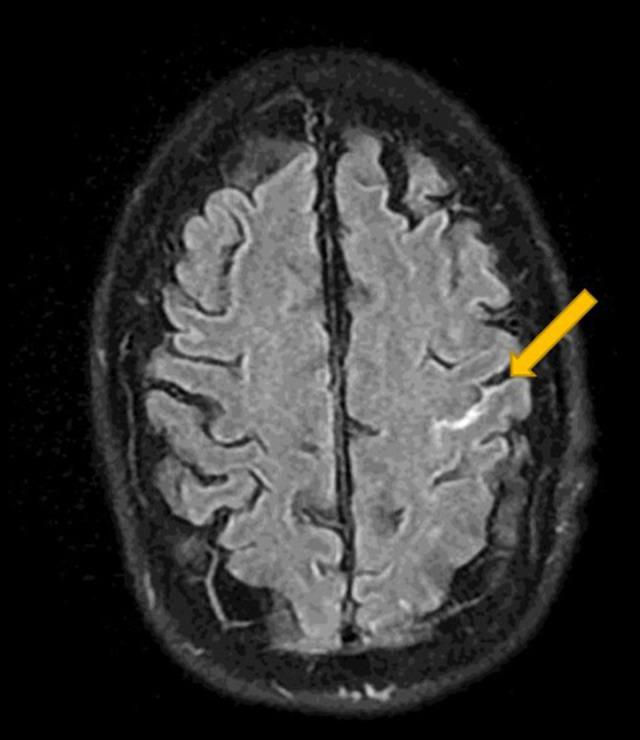

BACKGROUND Convexal subarachnoid hemorrhage (cSAH), a rare form of non-aneurysmal subarachnoid hemorrhage, is confined to cerebral convexities without extension into basal cisterns or ventricles. Typical presentation includes thunderclap/progressive headache or transient focal neurological symptoms; rare manifestations include seizures, intractable vomiting, or altered mental status. Here, we report the first case of convexal subarachnoid hemorrhage and multifocal ischemic lesions caused by infective endocarditis (IE) in a treatment-naïve advanced HIV patient. CASE REPORT A 52-year-old HAART-naïve, HIV-positive, African American man presented with altered mental status, shortness of breath, nonproductive cough, and generalized weakness. His past medical history was significant for congestive heart failure, chronic obstructive pulmonary disease, and end-stage renal disease (noncompliant with hemodialysis). Head computed tomography (CT) showed an isolated sulcal hemorrhage in the mid-left frontal lobe. Fluid-attenuated inversion recovery/gradient recalled echo sequences confirmed a hemorrhage in the left-mid-frontal sulcus, and diffusion-weighted imaging revealed multifocal bilateral ischemic lesions. Transesophageal echocardiography exhibited mitral valve vegetations. Multifocal ischemic lesions and cSAH caused by infectious endocarditis were confirmed. Initiation of intravenous vancomycin and piperacillin-tazobactam allowed the patient to have resolution of his altered mental status. A head CT 5 days later revealed the resolution of cSAH. CONCLUSIONS Infective endocarditis should be considered as an underlying etiology of cSAH, especially when present with multifocal ischemic lesions. Risk factors contributing to the development of cSAH in the IE patient population should be explored in future studies. HIV has not been previously reported in this subgroup and its prevalence should be considered. The prognosis for cSAH in relation to IE is generally favorable.

一名 52 岁的未接受抗逆转录病毒治疗(HAART)的、HIV 阳性、非裔美国男性,以意识状态改变、呼吸急促、非生产性咳嗽和全身无力为表现就诊。他的既往病史包括充血性心力衰竭、慢性阻塞性肺疾病和终末期肾病(未遵医嘱行血液透析)。头部计算机断层扫描(CT)显示左中额叶孤立性脑沟出血。液体衰减反转恢复/梯度回波序列证实左中额沟有出血,弥散加权成像显示双侧多灶性缺血性病变。经食管超声心动图显示二尖瓣有赘生物。诊断为感染性心内膜炎引起的多灶性缺血性病变和 cSAH。静脉万古霉素和哌拉西林他唑巴坦的使用使患者的意识状态改变得到改善。5 天后的头部 CT 显示 cSAH 已吸收。